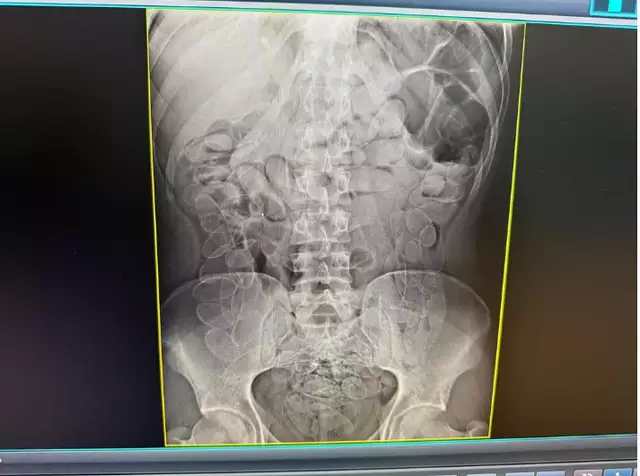

A mulher afirmou que ingeriu os invólucros ainda em território boliviano, há aproximadamente sete dias, permanecendo com o material no organismo durante todo o período. Um exame de raio-X abdominal identificou múltiplas cápsulas no estômago.

Inicialmente mantida sob observação, a paciente apresentou piora no quadro clínico e precisou ser submetida a cirurgia por volta das 18h. Durante o procedimento, os médicos retiraram as 90 cápsulas, com características semelhantes à cocaína.